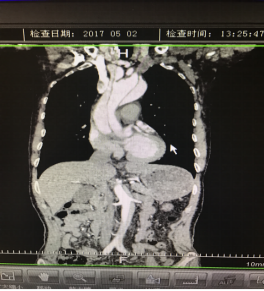

5月2號(hào)劉大伯照常早起干活,突然胸部劇烈疼痛,難以忍受,全身大汗,同時(shí)伴有右上肢發(fā)涼,他心想這次心絞痛比之前嚴(yán)重的多啊,趕緊叫上孩子到吉林國(guó)文醫(yī)院心血管內(nèi)科住院,患者長(zhǎng)期高血壓病史,血壓一直控制不理想,大夫給他做了檢查,測(cè)左上肢血壓:82/45mmHg,右上肢血壓測(cè)不出,心率52次/分,右側(cè)肱動(dòng)脈、尺動(dòng)脈、橈動(dòng)脈搏動(dòng)消失,左側(cè)股動(dòng)脈搏動(dòng)較右側(cè)弱?!霸懔?,雙側(cè)血壓差別這么大,是不是主動(dòng)脈夾層了?”,接診大夫趕緊找來(lái)李主任,李主任反復(fù)詢(xún)問(wèn)患者病情,表情突然凝重起來(lái),患者胸痛這么明顯,血壓低的厲害,主動(dòng)脈夾層的可能性很大。二話不說(shuō),李主任立即聯(lián)系影像科的醫(yī)生準(zhǔn)備做主動(dòng)脈CTA,移動(dòng)患者做檢查的過(guò)程大夫們非常小心,嚴(yán)密監(jiān)測(cè)患者血壓變化情況。兩個(gè)小時(shí)后結(jié)果出來(lái)了,主動(dòng)脈夾層從升主動(dòng)脈一直撕裂到左側(cè)髂總動(dòng)脈?。?!

從開(kāi)始學(xué)醫(yī)到現(xiàn)在已經(jīng)快9年了,主動(dòng)脈夾層患者也見(jiàn)過(guò)一些,但像劉大伯這種危險(xiǎn)類(lèi)型的還是第一次見(jiàn)到,心里真的為他捏把汗,撕裂的主動(dòng)脈隨時(shí)都有可能破裂,生命隨時(shí)可能終止,要知道主動(dòng)脈夾層的死亡率非常的高,約50%的患者發(fā)病后48小時(shí)死亡,約90%的患者發(fā)病1個(gè)月內(nèi)死亡。